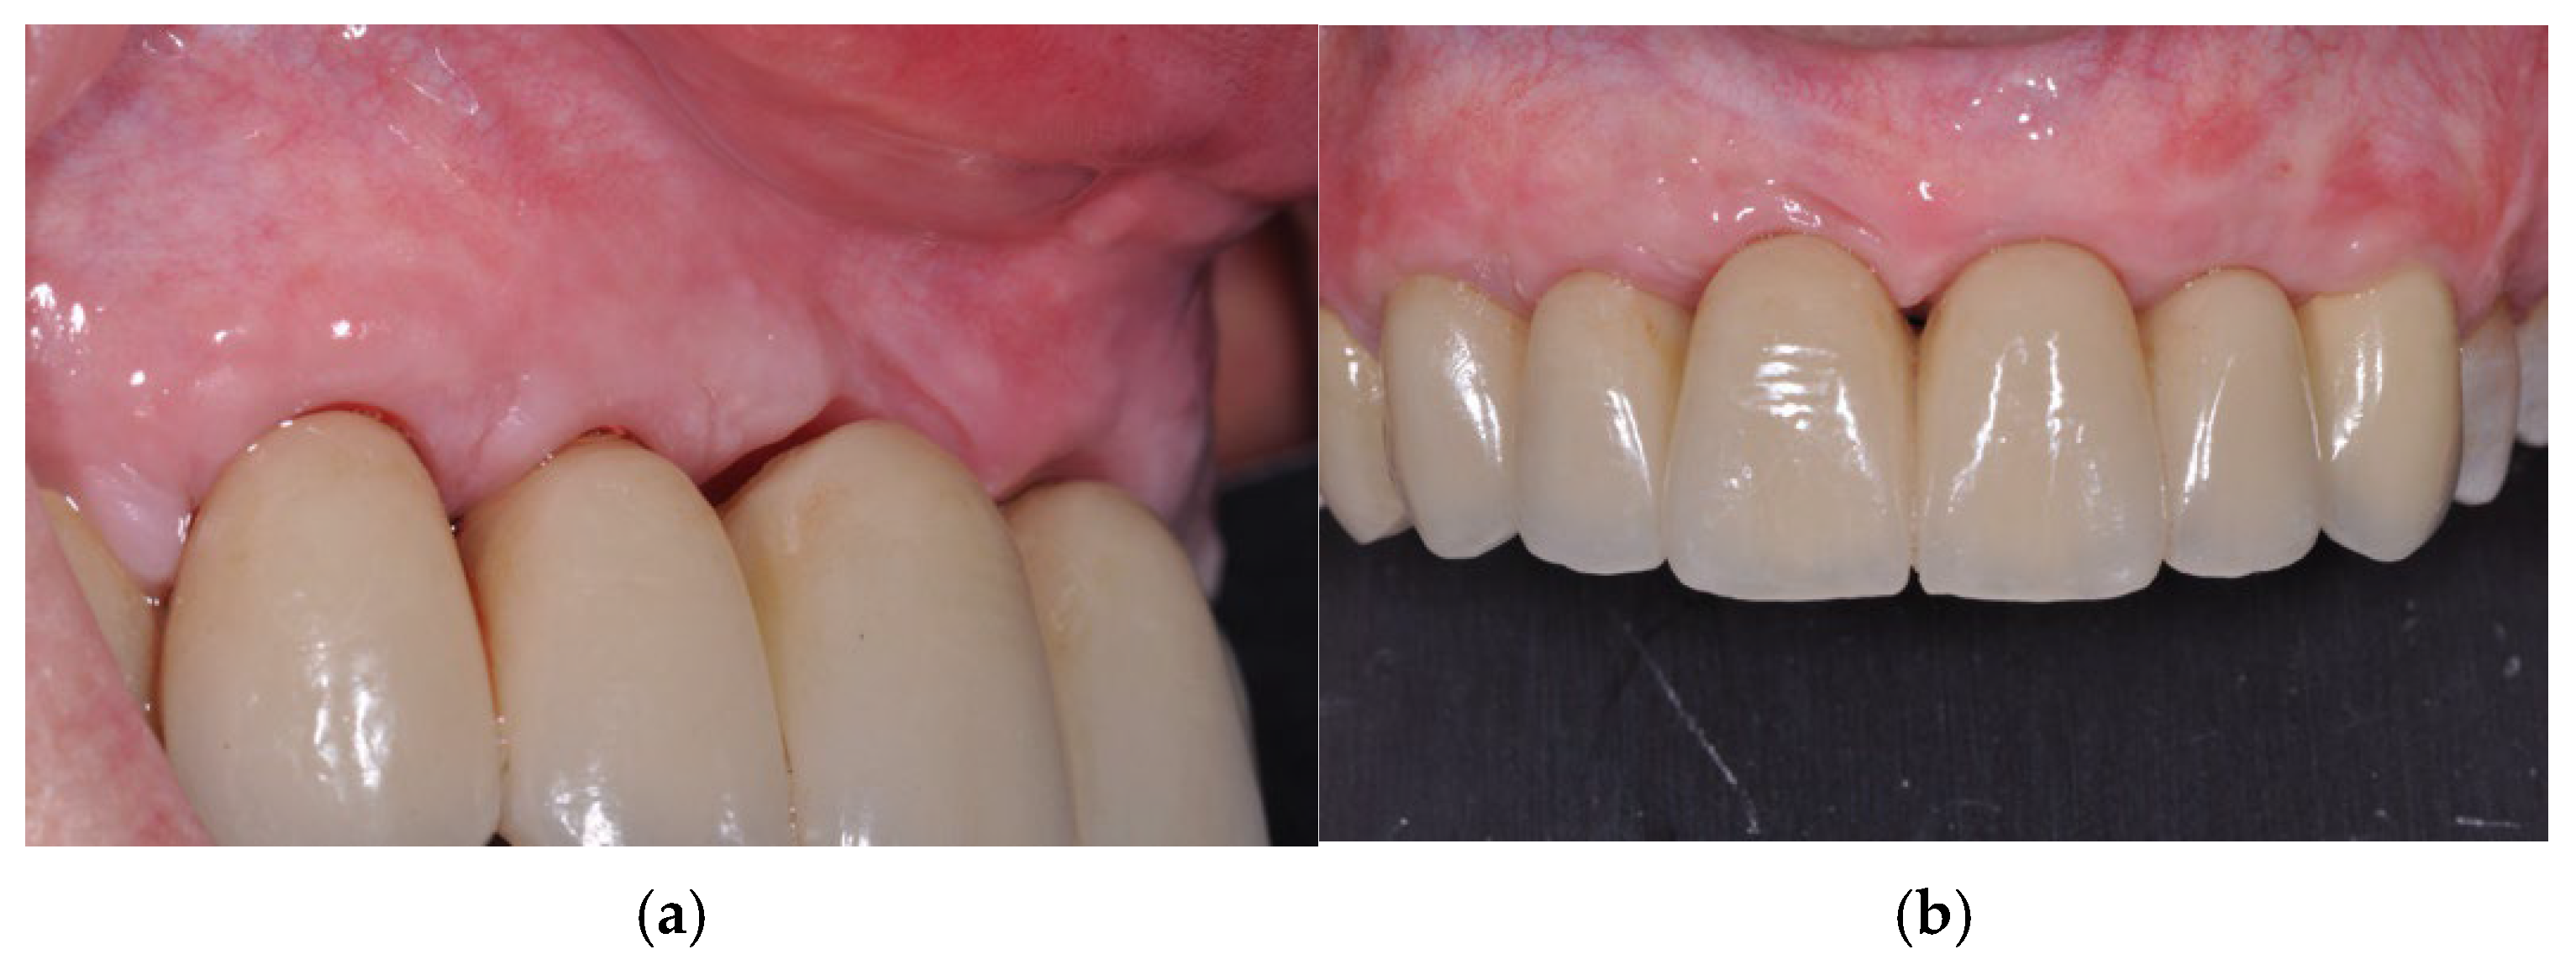

2. Methods

2.1. Case Presentation

2.2. Surgical Procedure

3. Results